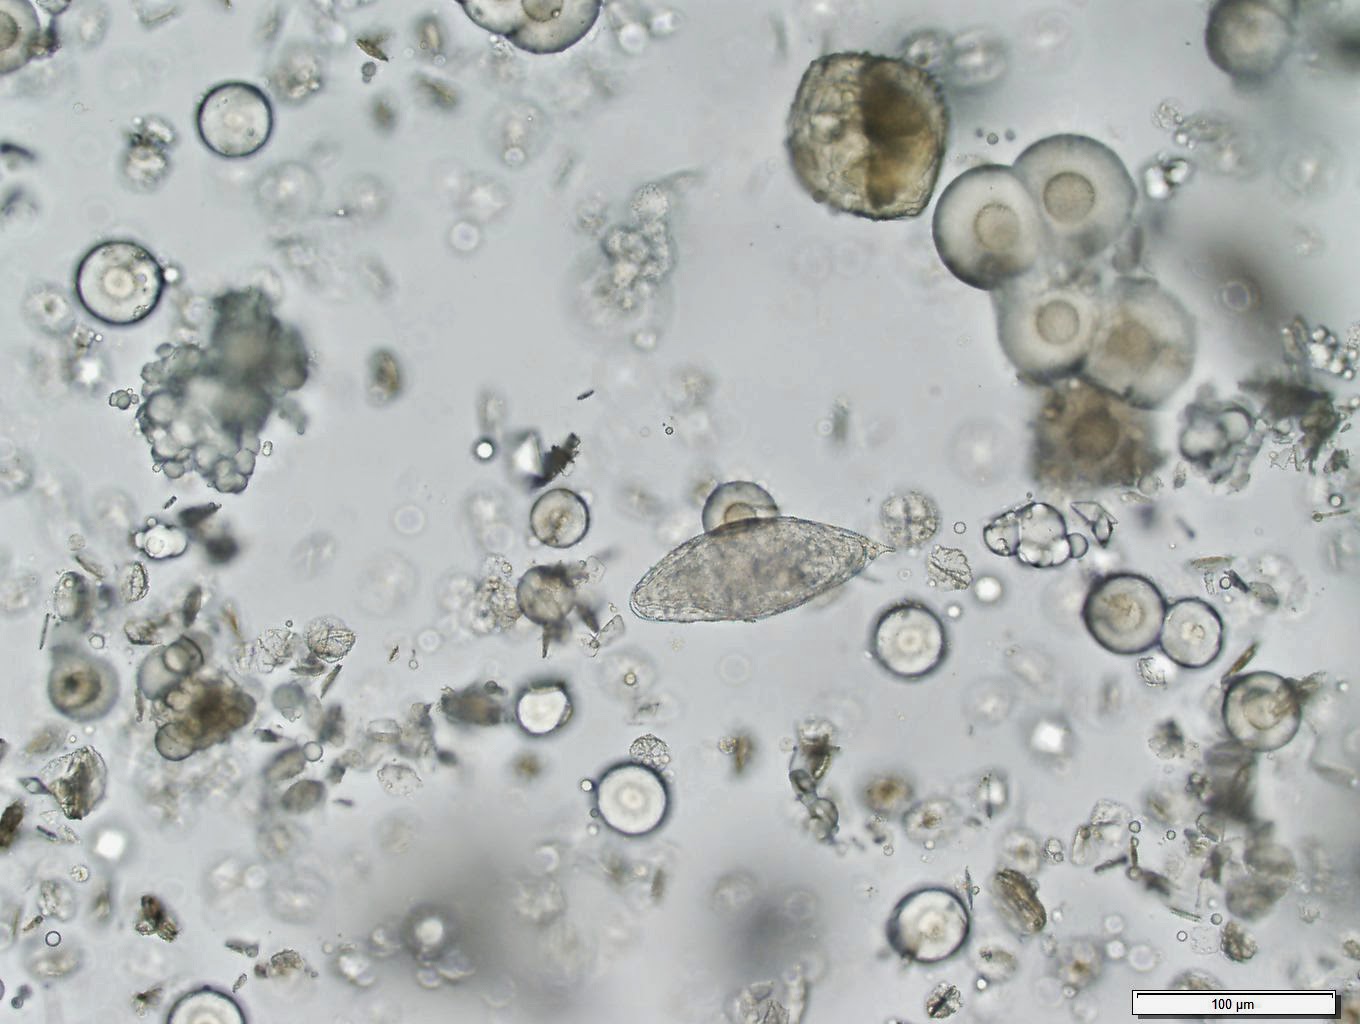

Schistosoma haematobium ova

Oh yes, the centrally located spine is characteristic of Schistosoma haematobium ova.

Terminal spine noted and usually found in urine.

Schistosoma H,wbc,yeast buds